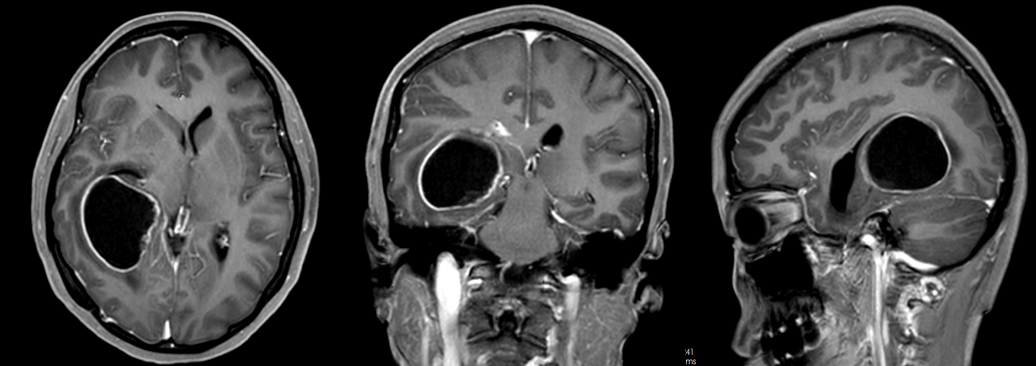

医院接诊时,患者的情况已不容乐观,头痛反复发作,伴有呕吐,逐渐陷入嗜睡状态。急诊完善磁共振,明确患者是颅内占位病变卒中出血,并形成右侧颞角脑积水进行性加重。

甘露醇脱水的效果越来越差,患者颅内这颗“炸弹”正在持续引爆,必须立即干预。医院果断为患者急诊行右侧颞枕叶占位病变切除术手术。

术前影像检查(图源广东三九脑科医院)

术后,林女士意识逐渐恢复清醒,而且四肢能够遵嘱活动。术后第十天,林女士顺利康复出院。